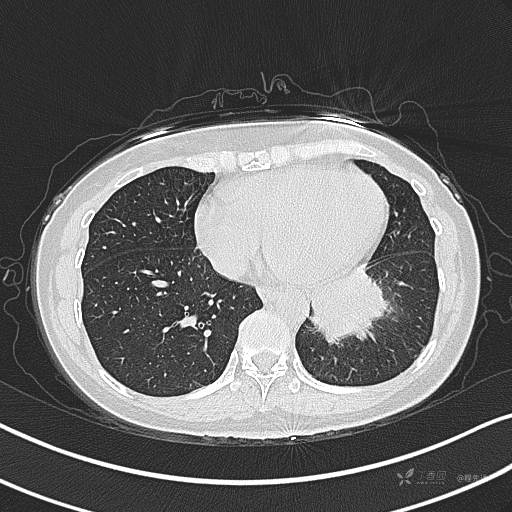

CT平扫

肺窗